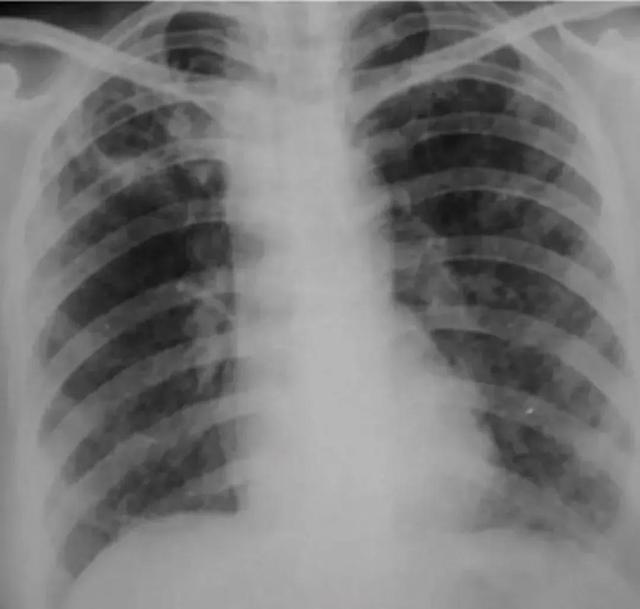

a.两上肺可见斑片状影,边缘模糊;b.右上肺可见片状及结节状高密度影,右肺门上提;c.右上肺可见斑片状密度增高影,边缘模糊;d.右上肺可见片状模糊影,其内可见两个薄壁空洞;e.两上肺斑片状及条索状影,右上肺可见多发小空洞,邻近胸膜增厚,两肺门上提,两下肺纹理呈垂柳状;

1.X线 继发型肺结核的X线平片表现与病变性质有关。

(1)渗出浸润为主型:病灶大多呈斑片状或云絮状,边缘模糊,好发于上叶尖后段和下叶背段,以尖后段最多见,病灶可单发或多发,局限于一侧或两侧肺尖和锁骨下区。病灶内密度减低区为病灶溶解、空洞形成的表现。空洞可为薄壁、张力性、干酪厚壁和纤维空洞等。有时可见空洞播散所致其他肺野的较广泛和散在的支气管播散灶,呈大小不等的斑点状和斑片状影。

(2)干酪为主型:包括结核球和干酪性肺炎。结核球为一种干酪性病变被纤维组织所包围而成的球形病灶,也可因空洞的引流支气管阻塞,其内为干酪物质所充填而成,呈圆形或椭圆形,称为结核球或结核瘤。好发于上叶尖后段与下叶背段,其他部位少见。多为单发,少数可多发大小多为2~3cm。结核球轮廓多较光滑,少数可呈切迹很浅的分叶状;密度较高且较均匀,但其内的干酪物质可液化并经支气管排除后形成空洞,其形态不一,以厚壁多见。部分结核球内可见成层的环形或散在的斑点状钙化。近胸膜的结核球,在病灶与胸膜间有时可见索条状粘连带。结核球邻近的肺野可见散在的增殖性或纤维性病灶,称为卫星病灶。干酪性肺炎为大量结核分鼓杆菌经支气管侵入肺组织而迅速引起的干酪样坏死性肺炎,表现为肺段或肺叶实变,轮廓较模糊,与大叶性肺炎相似,但以上叶多见。肺叶体积常因肺组织广泛破坏而缩小。有时在同侧和(或)对侧肺内,可见经支气管播散的小结节或斑片状边缘模糊阴影。

(3)空洞为主型:以纤维厚壁空洞、广泛的纤维性病变及支气管播散病灶组成病变的主体。该型患者痰中可查出结核分枝杆,,是结核病的主要传染源。锁骨上下区可见不规则慢性纤维空洞,周围伴有较广泛的条索状纤维性改变和散在的新老不一的病灶。在同侧和对侧肺内多可见斑点状的支气管播散病灶。由于广泛的纤维收缩,常使同侧肺门上提,肺纹理垂直向下呈垂柳状,可合并支气管扩张。未被病变所累及的肺野呈代偿性肺气肿表现。病灶邻多可见胸膜增厚粘连。广泛纤维化及胸膜增厚引起同侧胸廓塌陷,邻近肋间隙变窄,纵隔向患侧移位,肋膈角变钝,同时可伴有横膈圆顶幕状粘连。